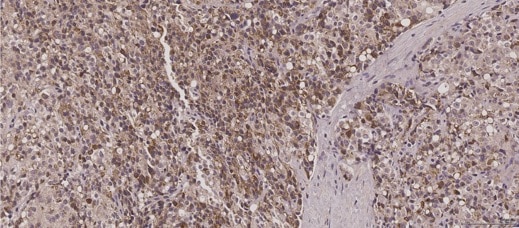

Immunohistochemistry: HIBCH Antibody (3H5) [NBP2-02673] - Human Prostate cancer tisuuse was stained using HIBCH antibody, showing the up-regulation of HIBCH. This image was submitted via customer Review.

Immunohistochemistry HIBCH NBP2-02673

IHC Human 06/15/2017

ApplicationImmunohistochemistry

Sample TestedProstate tissue

SpeciesHuman